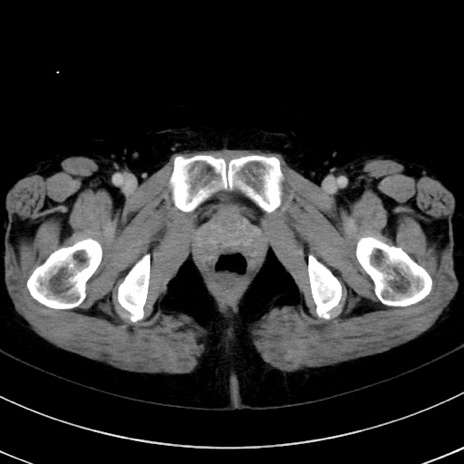

【腹部TIPS】症例99 CT(横断像)

【症例】50歳代女性

【現病歴】S状結腸癌術後のフォローCT

指摘するべき異常所見は?